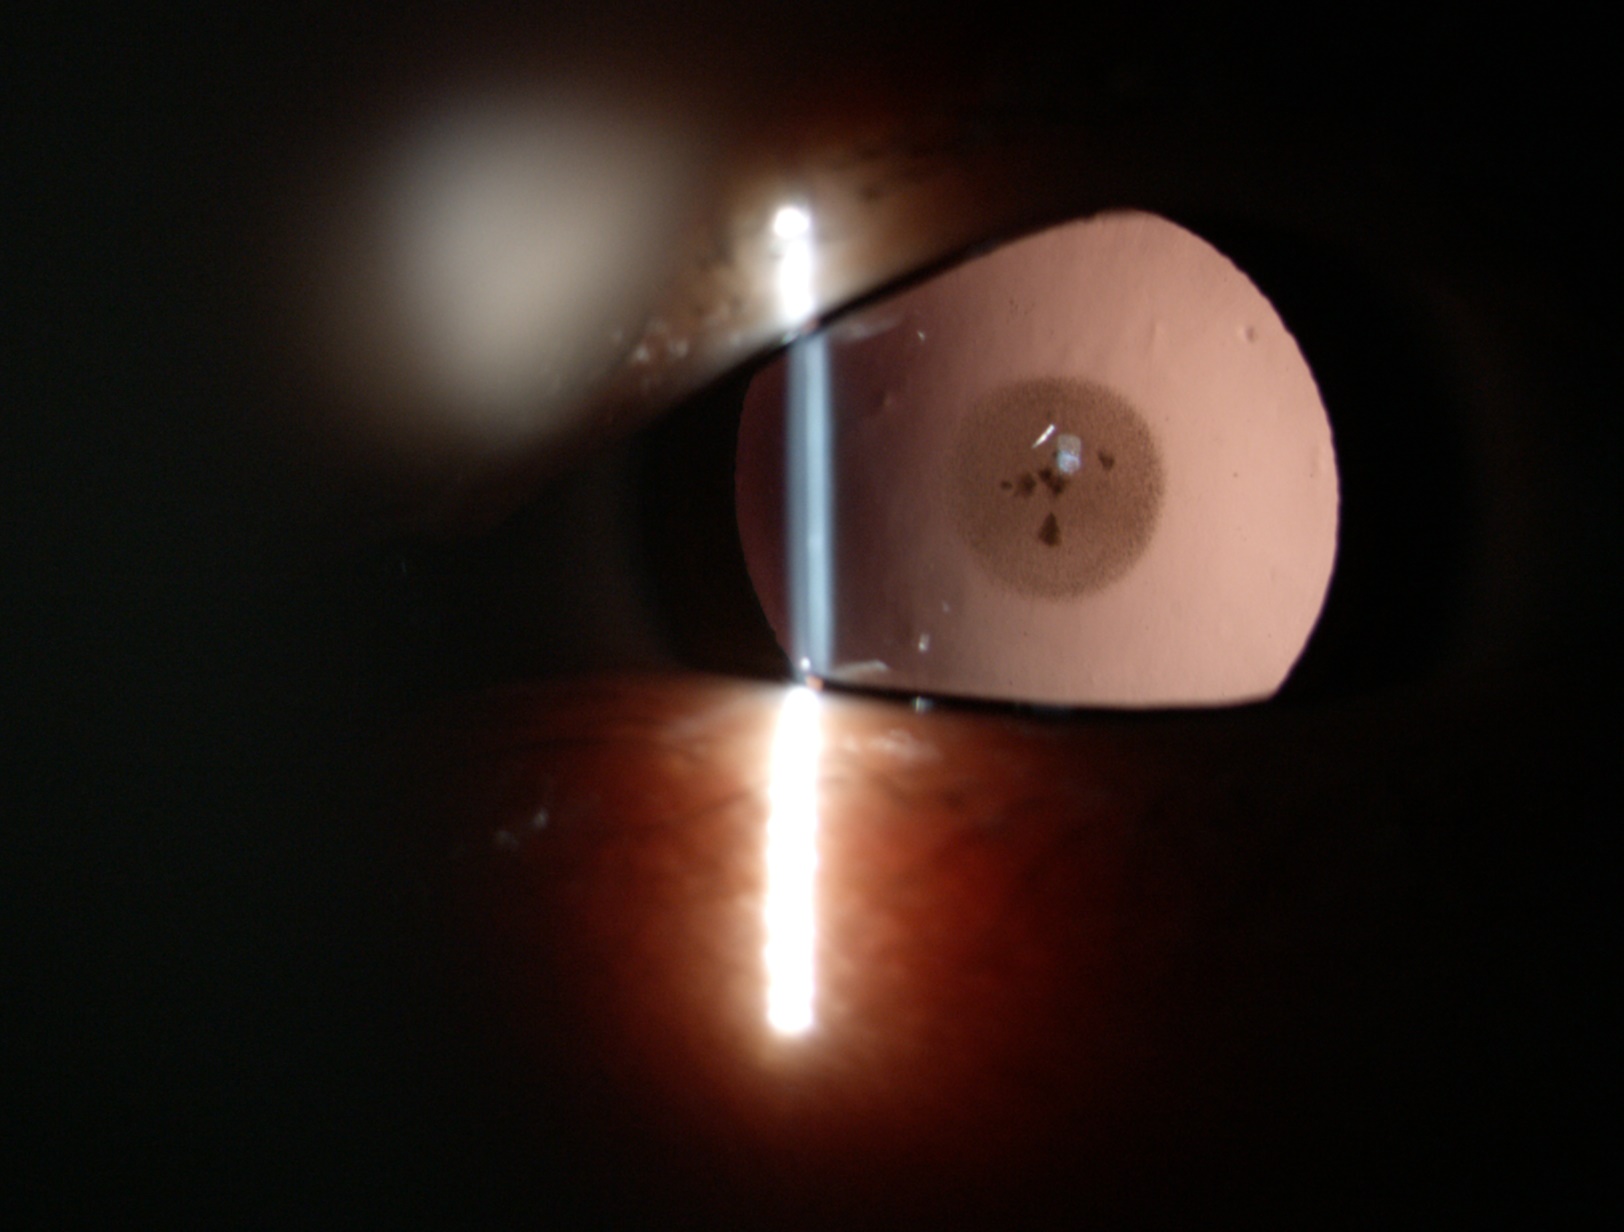

白內(nèi)障的手術(shù)效果好與不好

目前,沒有特效藥治療白內(nèi)障,即便有的藥物對(duì)早期的白內(nèi)障可起到緩解癥狀的作用,但無法逆轉(zhuǎn)病情,手術(shù)是治療白內(nèi)障有效的方法,通過將混濁的晶體蛋白清除,換上透明的人工晶狀體,才能讓白內(nèi)障患者重獲清晰視力。

白內(nèi)障的手術(shù)效果好與不好,主要與以下幾個(gè)因素有關(guān)。

白內(nèi)障癥狀